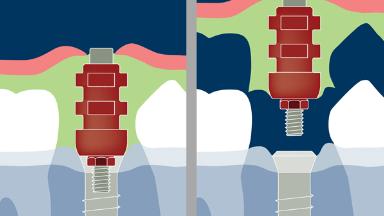

Moldagens de implantes são importantes para a confecção de próteses dentárias. O objetivo das moldagens de implantes é a transferência precisa da posição do implante intraoral para o laboratório dentário. É possível registrar a posição do implante com técnicas convencionais de moldagem analógica, ou com o uso de tecnologias digitais. Todas as técnicas de moldagem de implantes empregam uma variação da técnica de moldagem de arraste ou transferência, às vezes usada em prótese dentária convencional suportada por elementos dentários.

No caso de moldagens de implantes, um componente de alta precisão é usado para registrar a posição, o alinhamento e a orientação rotacional do implante. A moldagem, tanto se seguir um fluxo de trabalho convencional (ou seja, analógico) quanto digital, registra essa informação em relação aos tecidos duros e moles circundantes. Este módulo tratará das técnicas de moldagem convencionais e de todos os parâmetros envolvidos.

- definir os transferentes e técnicas de moldagem convencional de implantes

- descrever a técnica de moldagem específica para transferência do perfil de emergência de tecidos moles das próteses sobre implante